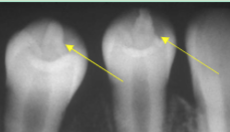

root resorption

shortened/ irregularly shaped root apex